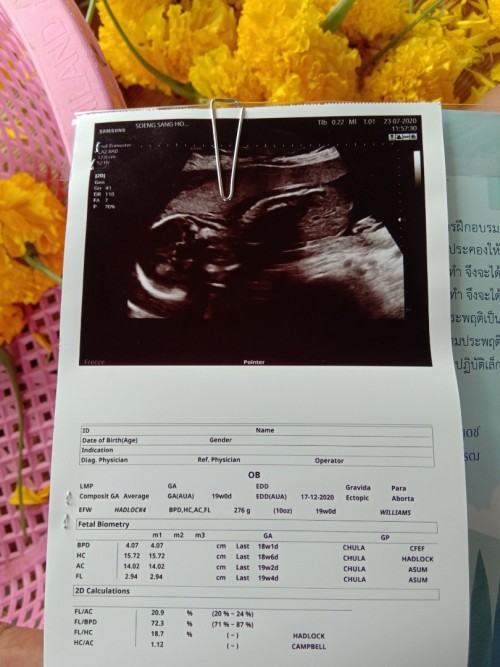

เพศชายกำหนดคลอด17ธันวาจ้า ซาวด์ตอน19w ปัจจุบัน27w 😁😁